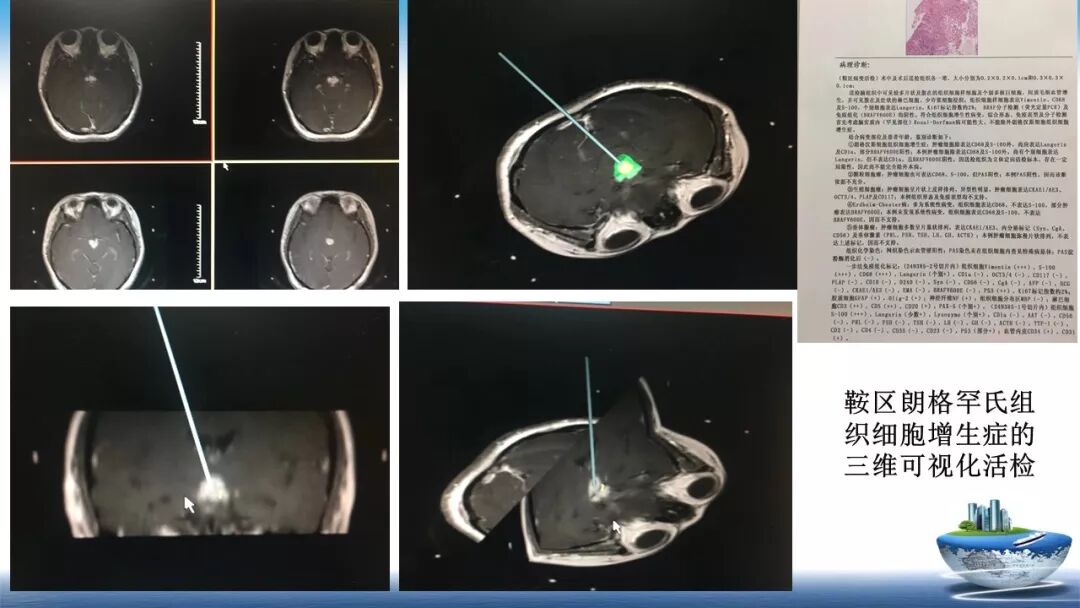

立体定向活检在脑干中线病变精准诊断中的作用

今天为大家带来的是中国人民解放军总医院第六医学中心(原中国人民解放军海军总医院)王亚明、于新、张剑宁带来的精彩课题分享:立体定向活检在脑干中线病变精准诊断中的作用,欢迎观看、阅读!